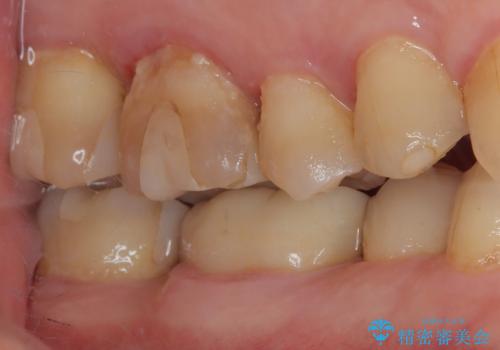

- 食事中に歯が欠けてしまった事を主訴に来院された患者様です。

小臼歯が広範囲に欠けてしまっています。

部分的な詰め物では再びかけてしまうリスクが高いため、オールセラミッククランにて補綴治療をすることとしました。